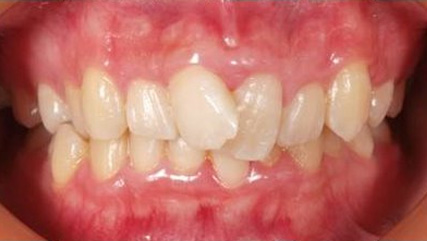

治療前

治療終了前